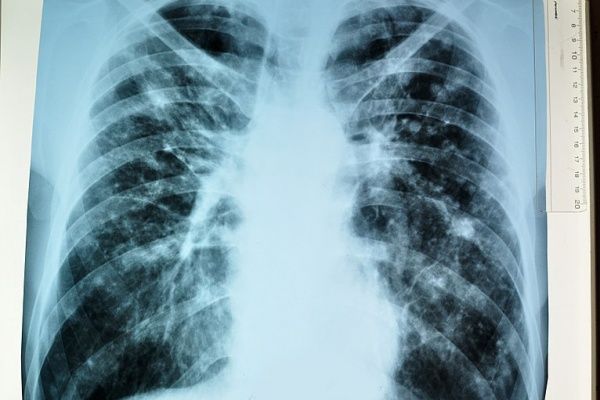

Туберкулез – заразное и коварное заболевание, передается от больного легочной формой чаще воздушно-капельным и воздушно-пылевым путем при кашле, чихании и разговоре.Туберкулезом может поражаться любой орган, но чаще всего легкие.

Признаки туберкулеза легких не специфичны, они могут быть и при других заболеваниях: отсутствие аппетита, снижение веса, общее недомогание, слабость, быстрая утомляемость, потливость по ночам, плохой сон, раздражительность, субфебрильная температура, кашель более двух недель, одышка, дискомфорт и боли в грудной клетке, кровохарканье.